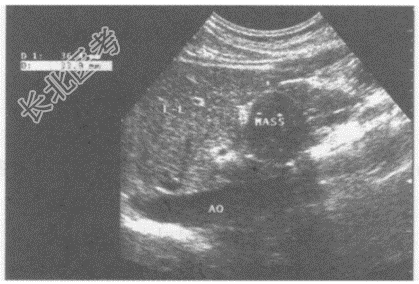

超声综合描述: 腹主动脉下腔静脉前方,胰头右侧可见3.6cm×3.4cm圆形低回声区, 边界清晰,包膜完整, 内回声尚均匀,CDFI: 内未明显血流信号,周边可见血管绕行。见下图及彩图。